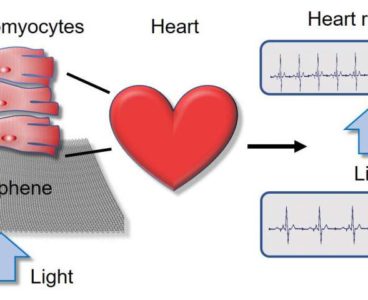

Researchers Operate Lab-Grown Heart Cells by Remote Control

Researchers at University of California San Diego School of Medicine and their collaborators have developed a technique that allows them to speed up or slow down human heart cells growing in a dish on command—simply by shining a light on them and varying its intensity. The cells are grown on a material called graphene, which…